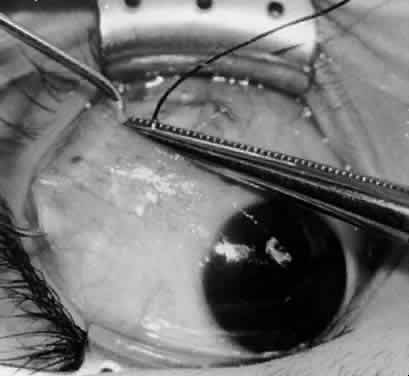

Fig. 15. The placement of sutures within the sclera for a recession procedure of 10 mm. The anterior suture is placed 3 mm temporal and 2 mm posterior to the lateral insertion of the inferior rectus muscle, and the posterior suture is placed 3 mm further posteriorly.

Fig. 16. Two sutures straddle the inferior temporal vortex vein insertion for a 14-mm recession procedure.

Fig. 17. Knots are tied to show the placement. The inferior oblique muscle is held on a Stevens muscle hook.